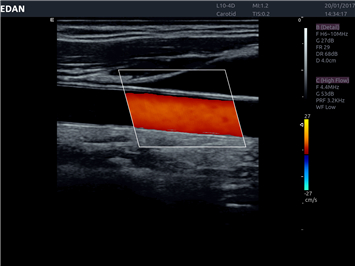

- Machine Type 4D Colour Doppler Ultrasound Machine

- Adaptive Doppler imaging Frequency Compounding Imaging ,- Adaptive Spatial Compounding Imaging ,- Harmonic Imaging ,- Adaptive Speckle Reduction Imaging (eSRI)

- Spectrum Enhancement ,- B mode Auto Optimization ,- Color mode Auto Optimization

- PW mode Auto Optimization